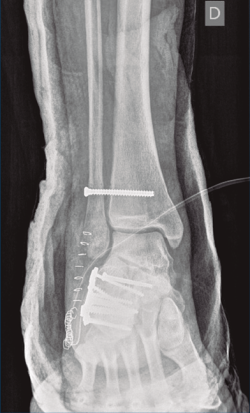

Bajo isquemia se realiza un abordaje lateral en L ampliado y se expone el calcáneo. Se trató de realizar una reducción abierta empleando un clavo de Steinmann (maniobra de Westhues), lo cual no se consiguió hasta la realización de un alargamiento percutáneo del Aquiles. Se comprobó bajo escopia la correcta reducción tanto de la fractura del calcáneo como de la luxación al nivel del tobillo. Se realizó una fijación con una placa de calcáneo, con 7 tornillos de esponjosa de 4 mm de diámetro (2 de ellos bloqueados) tras la reducción de la carilla posterior con un tornillo a compresión de 3,5 mm.

A continuación, pasamos a realizar un segundo abordaje lateral, respetando una separación suficiente para minimizar el riesgo de necrosis cutánea, a través de la cual se reparó la rotura del complejo ligamentoso lateral y se fijó la sindesmosis con un tornillo transindesmal de 4 mm de diámetro tras comprobarse bajo escopia la lesión al nivel de la articulación tibioperonea distal. Se inmovilizó mediante una férula posterior a 90°.

Figura 9. Control radiográfico posquirúrgico, anteroposterior.

Se dio de alta el día siguiente a la cirugía con un buen control analgésico. En la radiografía de control postoperatoria presentó una correcta reducción tanto de la fractura de calcáneo como de la articulación tibioperoneo astragalina (Figuras 9 y 10). Se citó en consultas externas 2 semanas después para la retirada de la sutura, presentado un buen aspecto las heridas quirúrgicas (Figura 11), y para la colocación de un botín de yeso. Dicho botín fue retirado al mes y medio de la cirugía, colocándose una ortesis estabilizadora de tipo Walker y autorizándose la carga parcial y progresiva, comenzando la rehabilitación.

A los 9 meses únicamente presentó dolor ocasional al nivel de la articulación subastragalina y molestias en la planta del pie al deambular descalzo, por lo que se pauta plantilla amortiguadora, con la que mejora notablemente la sintomatología. Presentó una puntuación de 83 sobre 100 en la escala de la American Orthopaedic Foot and Ankle Society (AOFAS), ligeramente superior a la media descrita en estudios previos(2,3). Radiográficamente se evidenció una anatomía restablecida del calcáneo y de la sindesmosis, así como una altura adecuada de ambos tobillos (Figuras 12 y 13). Dada la buena evolución, se decidió continuar con el seguimiento anual del paciente sin realizar la extracción del material de osteosíntesis, para valorar la necesidad de una futura artrodesis sub­astragalina.